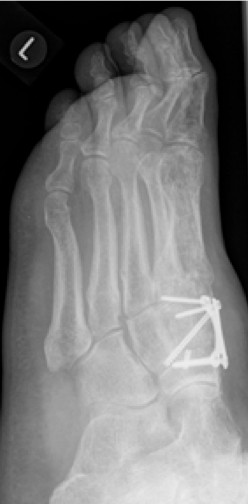

2.-Postoperatives Bild Februar 2017

Im Rahmen einer Verlaufskontrolle zeigte sich ein Schraubenbruch als Zeichen einer fehlenden Durchbauung der Arthrodese.

3.- April 2017: Schraubenbruch